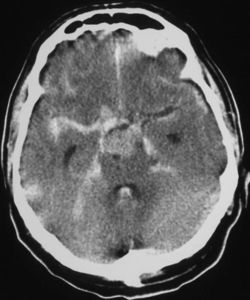

The Fisher Grade classifies the appearance of subarachnoid hemorrhage on CT scan:[4]

- Grade 1: No hemorrhage evident

- Grade 2: Subarachnoid hemorrhage less than 1 mm thick

- Grade 3: Subarachnoid hemorrhage more than 1 mm thick

- Grade 4: Subarachnoid hemorrhage of any thickness with intra-ventricular hemorrhage (IVH) or parenchymal extension